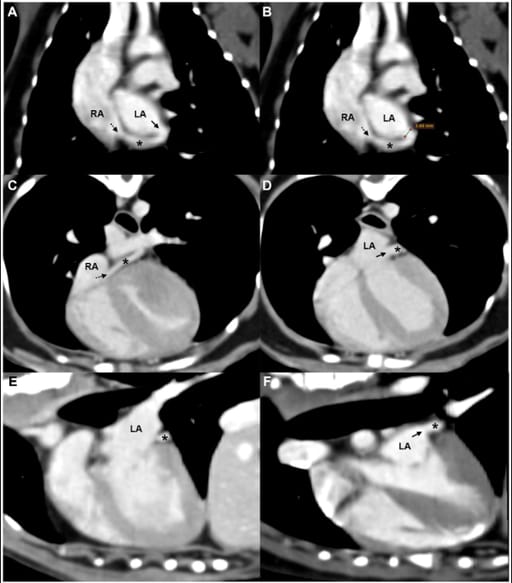

TTE showed a prominently visualized tubular structure compatible with the coronary sinus and continuous flow entering the right atrium (velocity ~0.5 m/s), without an atrial septal defect; Qp/Qs was 1.3, and a bubble study excluded a right-to-left shunt. CT confirmed a 3.6-mm partial defect between the mid-coronary sinus and the left atrium with similar contrast enhancement of both chambers, supporting a left-to-right shunt; no additional congenital anomalies were detected. Based on defect location and absence of persistent left superior vena cava, the lesion corresponds to a partially unroofed midportion (Type III by classic scheme; Type IIb by the Xie modification). Serial echocardiographic follow-up was recommended. WES highlighted four unique missense SNVs—CEP250, HHEX, CSPG4, CDK15—as candidate variants.

Oblique reformatted CT images of the (A,B) dorsal, (C,D) axial, and (E,F) sagittal planes showing a partial defect between the coronary sinus and the LA. A tubular structure consistent with the coronary sinus (asterisk) courses along the posterior aspect of the LA and drains into the RA via the coronary sinus ostium (black dashed arrow). A partial defect (black solid arrow) in the septum between the coronary sinus and LA is visible in panels (A,D,F), with similar contrast enhancement noted between the two chambers. Measurement of the defect is shown in panel (B). LA, left atrium; RA, right atrium; *, coronary sinus.